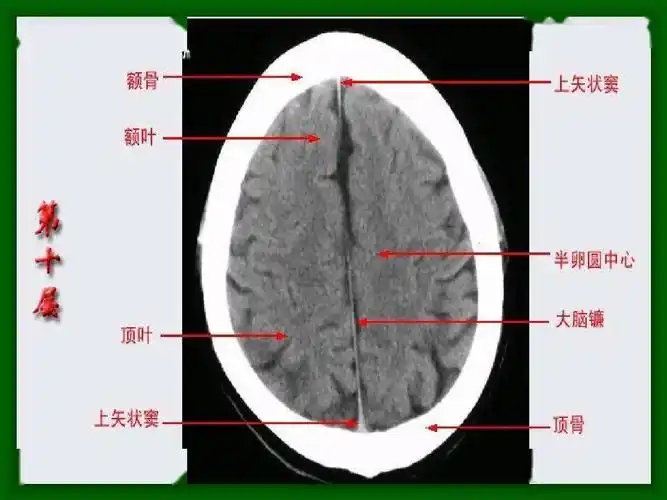

值班必备 | 急诊颅脑ct常见的八种疾病

皓月ct头颅图像技术和样片分享

头颅ct扫描时如何打角度才能看得更多更清晰